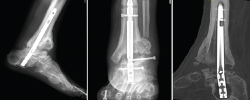

Se le realizó una ATTC mediante abordaje lateral transperoneal para el legrado de las articulaciones tibiotalar y subtalar, y fijación con un clavo tibiotalocalcáneo (TTC) retrógrado modelo Phoenix® (Zimmer Biomet) de 180 mm de longitud y diámetro de 11 mm. Ante el retraso de la consolidación, el clavo se dinamizó a los 6 meses de la implantación retirando el tornillo de bloqueo proximal. A los 15 meses se observó falta de fusión tanto de la articulación tibiotalar como subtalar y rotura del clavo con extrusión del tornillo de bloqueo del astrágalo (Figura 1).

Figura 1. Imágenes radiográficas donde se observa rotura del clavo y extrusión del tornillo del astrágalo con ausencia de fusión. En la tercera imagen, proyección sagital de tomografía computarizada.